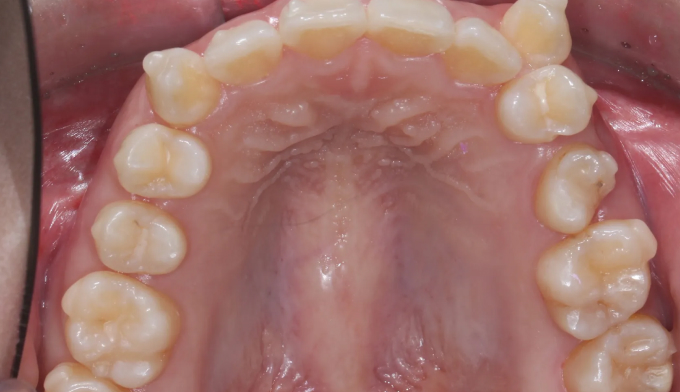

댜른치과에서 투명교정(인비절라인)치료를 받던 중 치료가 잘 진행되지 않고, 교정기간이 무기한으로 길어진다고 하였습니다.

해당 환자의 구강스캔을 다시 진행하고 현시점부터 재치료하기로 결정하였습니다.

덧니가 배열될 수 있는 공간을 먼저 만들기 위해 어금니들을 뒤로 먼저 보내고 미니스크류를 추가적으로 식립하여 보다 더 효과적인 치아이동이 가능하게 만들었습니다.

총 치료기간은 13개월입니다.